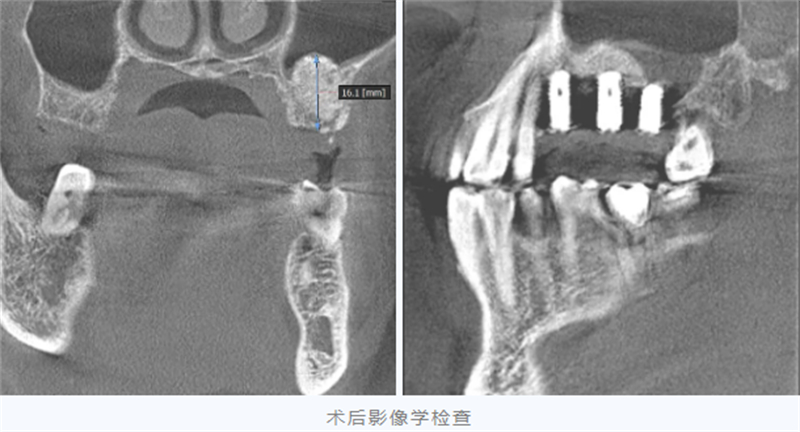

在任叔叔的信任與配合下,團隊順利為他施行了上頜骨外提升術并同期植入人工骨粉。

手術成功將骨高度從原來的約2毫米提升至10-12毫米,為種植體的植入奠定了更扎實的基礎。